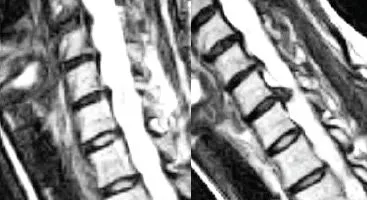

Multiple Disc Herniations Lumbar Spine

John developed severe debilitating lower back pain after lifting improperly. His pain continued for weeks and worsened after doing housework, radiating down his left leg. He couldn’t stand without leaning forward and his leg felt weak and unstable.